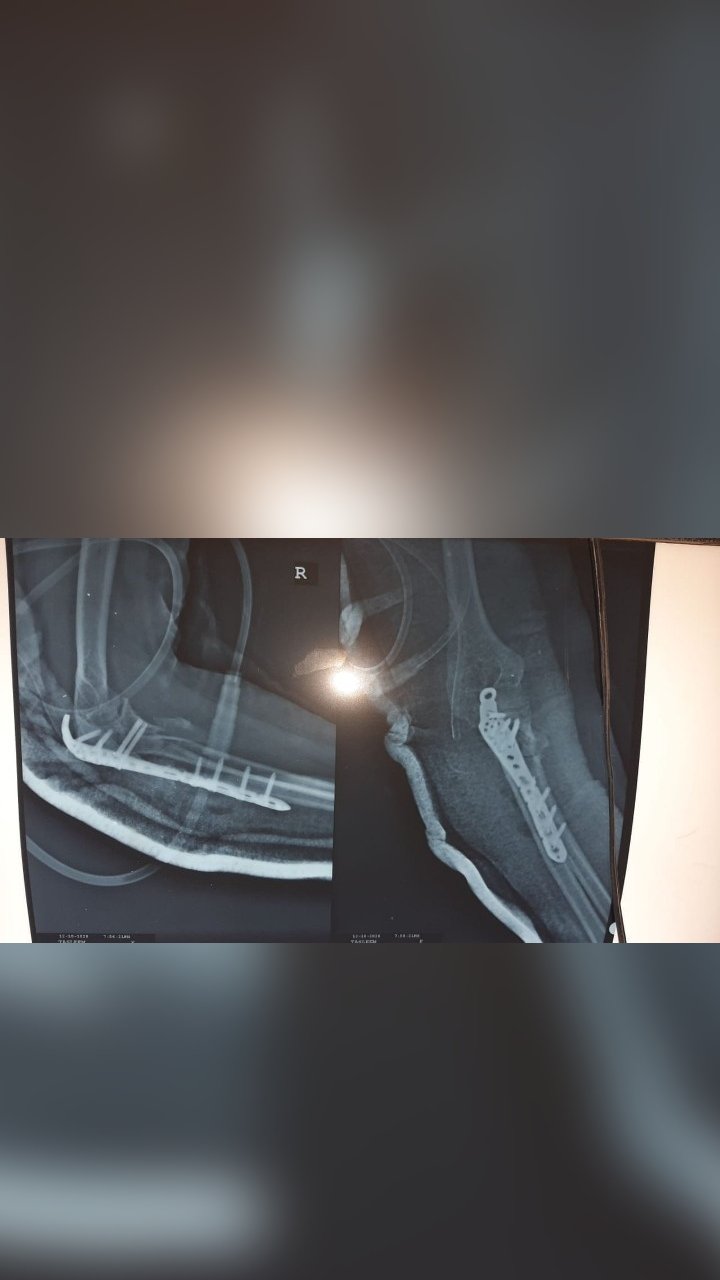

WRIST ARTHRODESIS

ELBOW AND FOREARM FRACTURE SURGERY